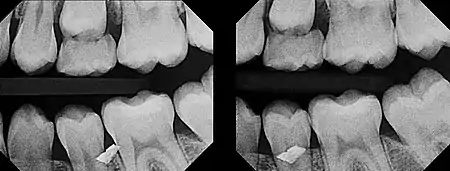

In 1909, Clark described a radiographic procedure for localizing impacted teeth to determining their relative antero-posterior position.[1] If the two teeth (or, by extension, any two objects, such as a tooth and a foreign object) are located in front of one another relative to the x-ray beam, they will appear superimposed on one another on a dental radiograph, but it will be impossible to know which one is in front of the other. To determine which is in front and which is behind, Clark proposed his SLOB rule, as a complicated set of three radiographs, but which can be simplified as follows using just two:

- Expose another film while angle of the x-ray beam has been changed. If an object moves in the same direction as the source of the x-ray beam, it is lingual to the other object. If the object moves in the opposite direction of the source, it is buccal to the other object.

In 1952, Richards amended this rule using only 2 radiographs,[2][3] asserting that the object positioned more buccally will move more relative to the object positioned more palatally or lingually.

As a generalization, but not specifically stated as part of Richards' buccal object rule, the more buccal an object is (i.e. the closer it is to the x-ray source) the more it will move in the second radiograph when repositioning the x-ray source.